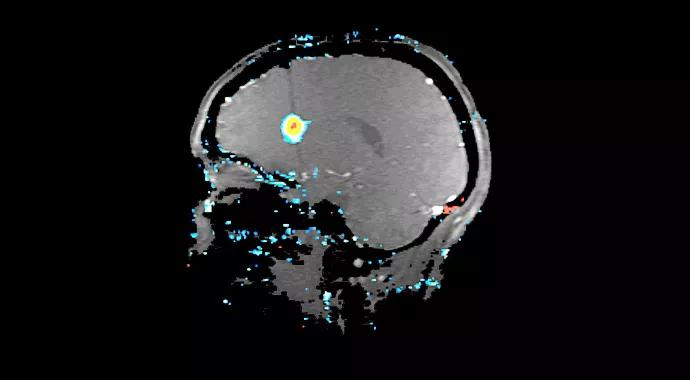

The laser was powered at 9W for approximately 60 seconds. Real-time thermal mapping was superimposed on MRI and refreshed every four seconds (Figure 2). Creation of an approximately 1-cm lesion was confirmed both on intraoperative diffusion imaging and on postprocedure gadolinium-enhanced T1-weighted imaging (Figure 2).

Figure 2. Intraprocedure ablation superimposed on T1-weighted images with temperature readings based on real-time thermal mapping algorithms. Panels A and B are intraoperative MRIs (coronal and sagittal T1 sequence images) with the laser probe in position. Panels C and D depict the initial (test) phase of the laser ablation procedure, showing the rise of temperature in the right periventricular region. Panels E and F show ablation in progress, with isothermal areas located in the right frontal periventricular region, in the location of the periventricular nodule. Panel G is a post-ablation contrast-enhanced MRI with a ring-enhancing lesion in the location of the right periventricular nodule.

Post-ablation MRI showed complete ablation of the focal periventricular heterotopic lesion, with an approximately 1-cm ellipsoid lesion created by the applicator. A gadolinium-enhancing rim (Figure 2G) shows the sharp delineation between normal brain and the lesion, with significant drop-off in heat between these areas as planned and described above.